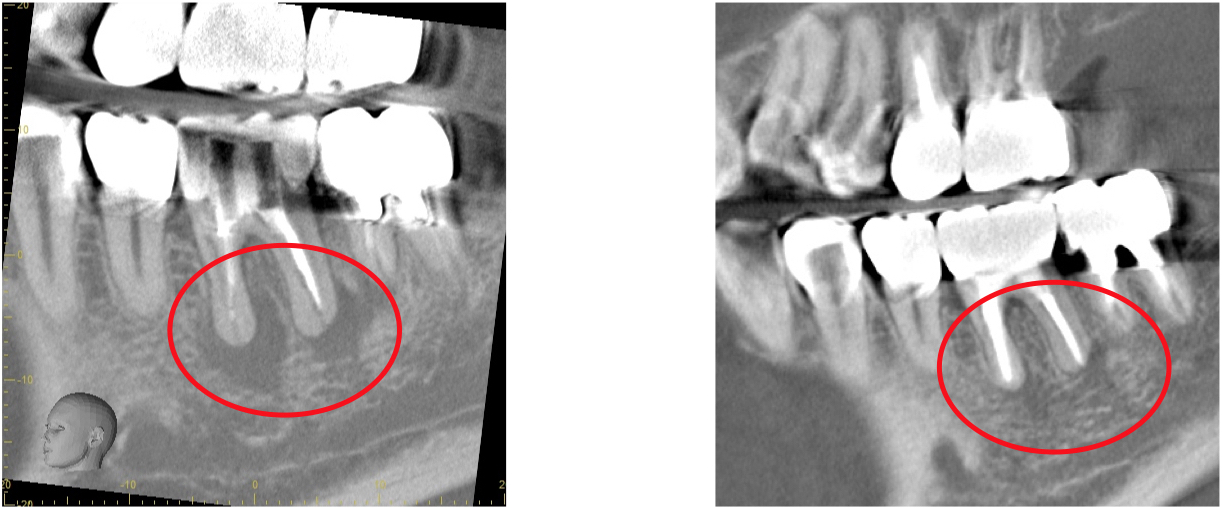

歯科用CTとは一般の医療用CTを歯科治療用に特化した装置です。

当院ではこの歯科用CTを使用して三次元で歯の構造を把握します。

任意の角度や位置から歯・顎骨を確認することもできるので治療の精度が大幅に向上します。